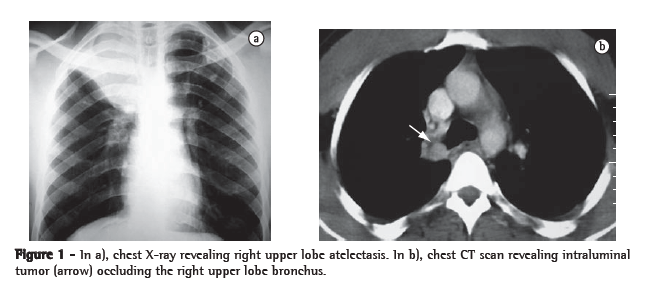

Case reportA 32-year-old male reported fever and dry cough 9 months prior to admission. On that occasion, he received treatment for pneumonia elsewhere, but the dry cough remained. The physical examination revealed right-sided wheezing, and a chest X-ray showed right upper lobe atelectasis (Figure 1a). A chest CT scan revealed an endobronchial lesion occluding the right upper lobe bronchus (Figure 1b), with no mediastinal lymph node enlargement. Fiberoptic bronchoscopy revealed an endobronchial tumor located in the right upper lobe bronchus. The tumor had a smooth, reddish surface and had obstructed the right upper lobe bronchus, without protruding into the right main bronchus. A biopsy provided inconclusive results. The patient underwent right thoracotomy with a presumed diagnosis of carcinoid tumor. Since the right upper lobe was atelectatic and fibrotic, we proceeded to a right upper lobectomy. The intraoperative histological examination demonstrated exiguous bronchial margins, and a wedge bronchoplasty was therefore performed. Radical mediastinal lymph node dissection was not performed. The patient had an uneventful recovery and was discharged on the fourth postoperative day.